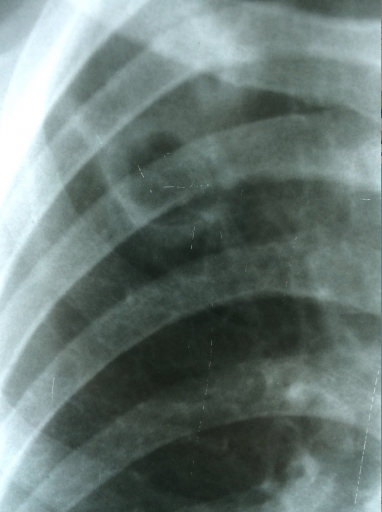

Симптомы и лечение инфильтративного туберкулеза легких

Раздел: Снимки-откровения